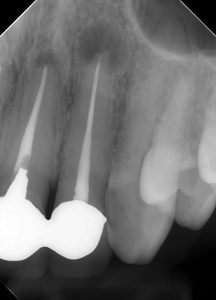

レントゲンを見てみよう。

(術前のレントゲン、CT)

右上2、左上1、左上2に根尖病変がある。

また、左右2番の根尖部に圧痛を認めた。

過去の根管治療ではラバーダムは使用していなかったとのこと。

4本の根管治療のうち、3本が失敗し、根尖病変ができている。